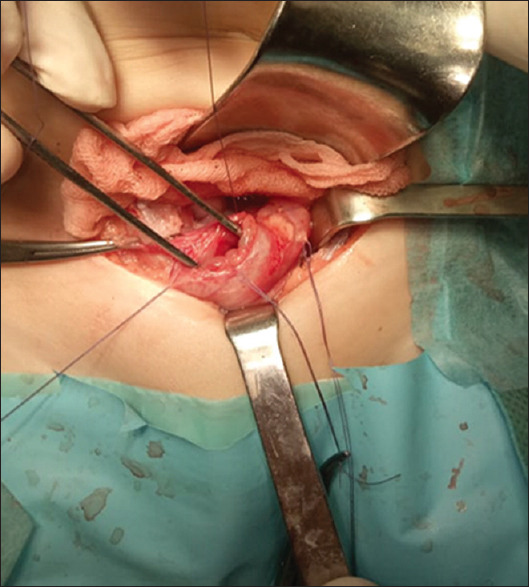

Abstract: Iatrogenic bladder rupture in children during a retrograde cystourethrography is very uncommon. We present a case of iatrogenic intraperitoneal bladder rupture in a 9-month child during the retrograde cystourethrography performed by a radiologist. The child presented in a paediatric emergency after 6 h with an acute abdomen indicating urinary peritonitis. An urgent laparotomy was performed and the perforation was repaired in two layers. The follow-up was unremarkable. This report emphasises the importance of respecting the criteria of the proper retrograde cystourethrography imaging procedure.